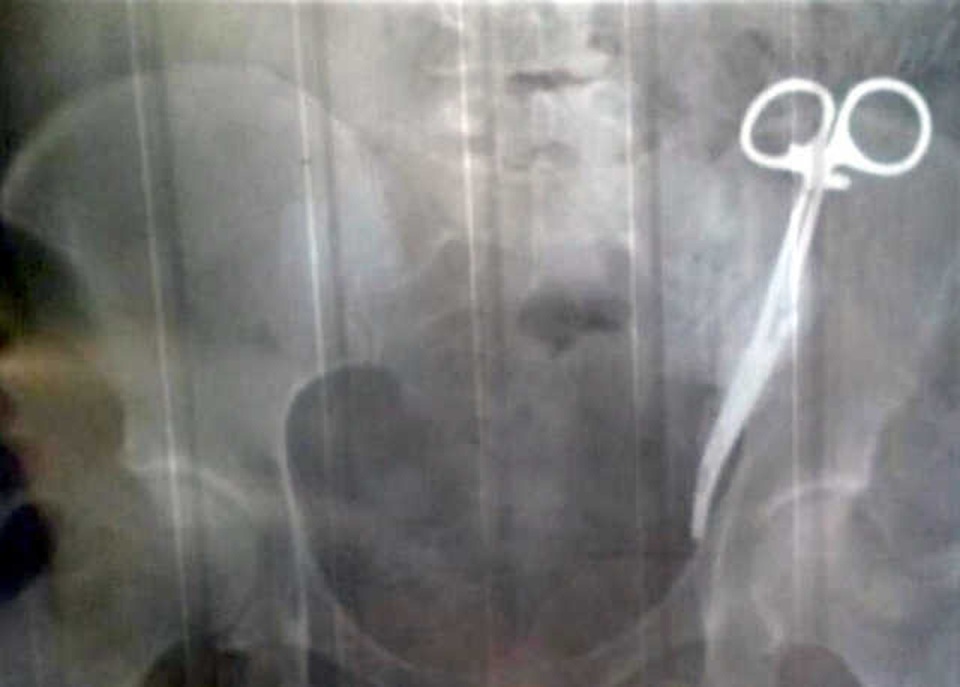

Kẹp phẫu thuật, trông giống như một chiếc kéo, được sử dụng để giữ các mô và gạc phẫu thuật, bị bỏ quên trong cơ thể bà Ezeta.

Kiểm tra cho thấy cơn đau là do một chiếc kẹp phẫu thuật bị kẹt lại trong bụng. Gobeeva cho rằng nó hẳn đã bị bỏ quên ở đó từ ca mổ lấy thai của các bác sĩ 23 năm về trước.

Kẹp phẫu thuật, trông giống như một chiếc kéo, được sử dụng để giữ các mô và gạc phẫu thuật, vẫn còn trong cơ thể Ezeta. Cuối cùng bà cũng được lên kế hoạch cho một ca phẫu thuật để lấy kẹp ra khỏi cơ thể.